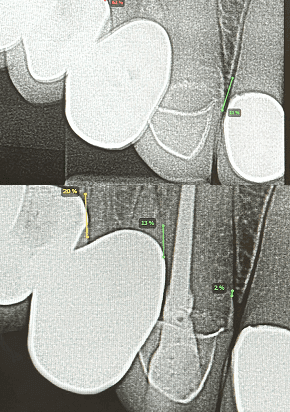

My mission is to offer excellence for you and your family, combining care, technology, and a truly human touch. I believe in individualized treatment, where each patient is unique and their needs are the priority. With an integrative approach, we look beyond the teeth to care for your overall health and well-being.